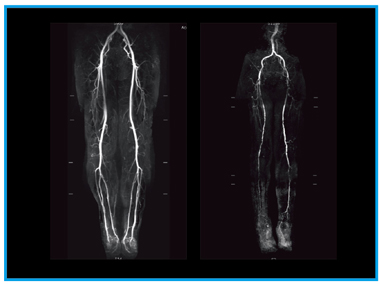

●心血管系(図5,6)

心血管系はまだコイルが納入されていないため,通常のBody用コイルにて仮運用を行っている。下肢の非造影MRAでは,狭窄例においてもある程度の臨床評価が可能であった。腎機能が悪く造影剤を使用できない患者に対しては,治療適応決定の際に非常に有効な方法であり,今後の発展に期待したい。また,心臓のMRIでは,従来よりもbandingアーチファクトが少ない印象がある。

![]() 図5 下肢の非造影MRA |